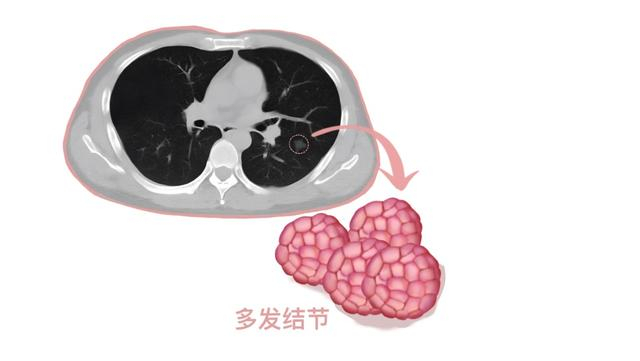

误区:多发肺结节没得治了

错!体检发现的多发肺结节,大部分是微小实性结节,多数为陈旧性病灶。如果是多发磨玻璃结节,部分与感染有关。